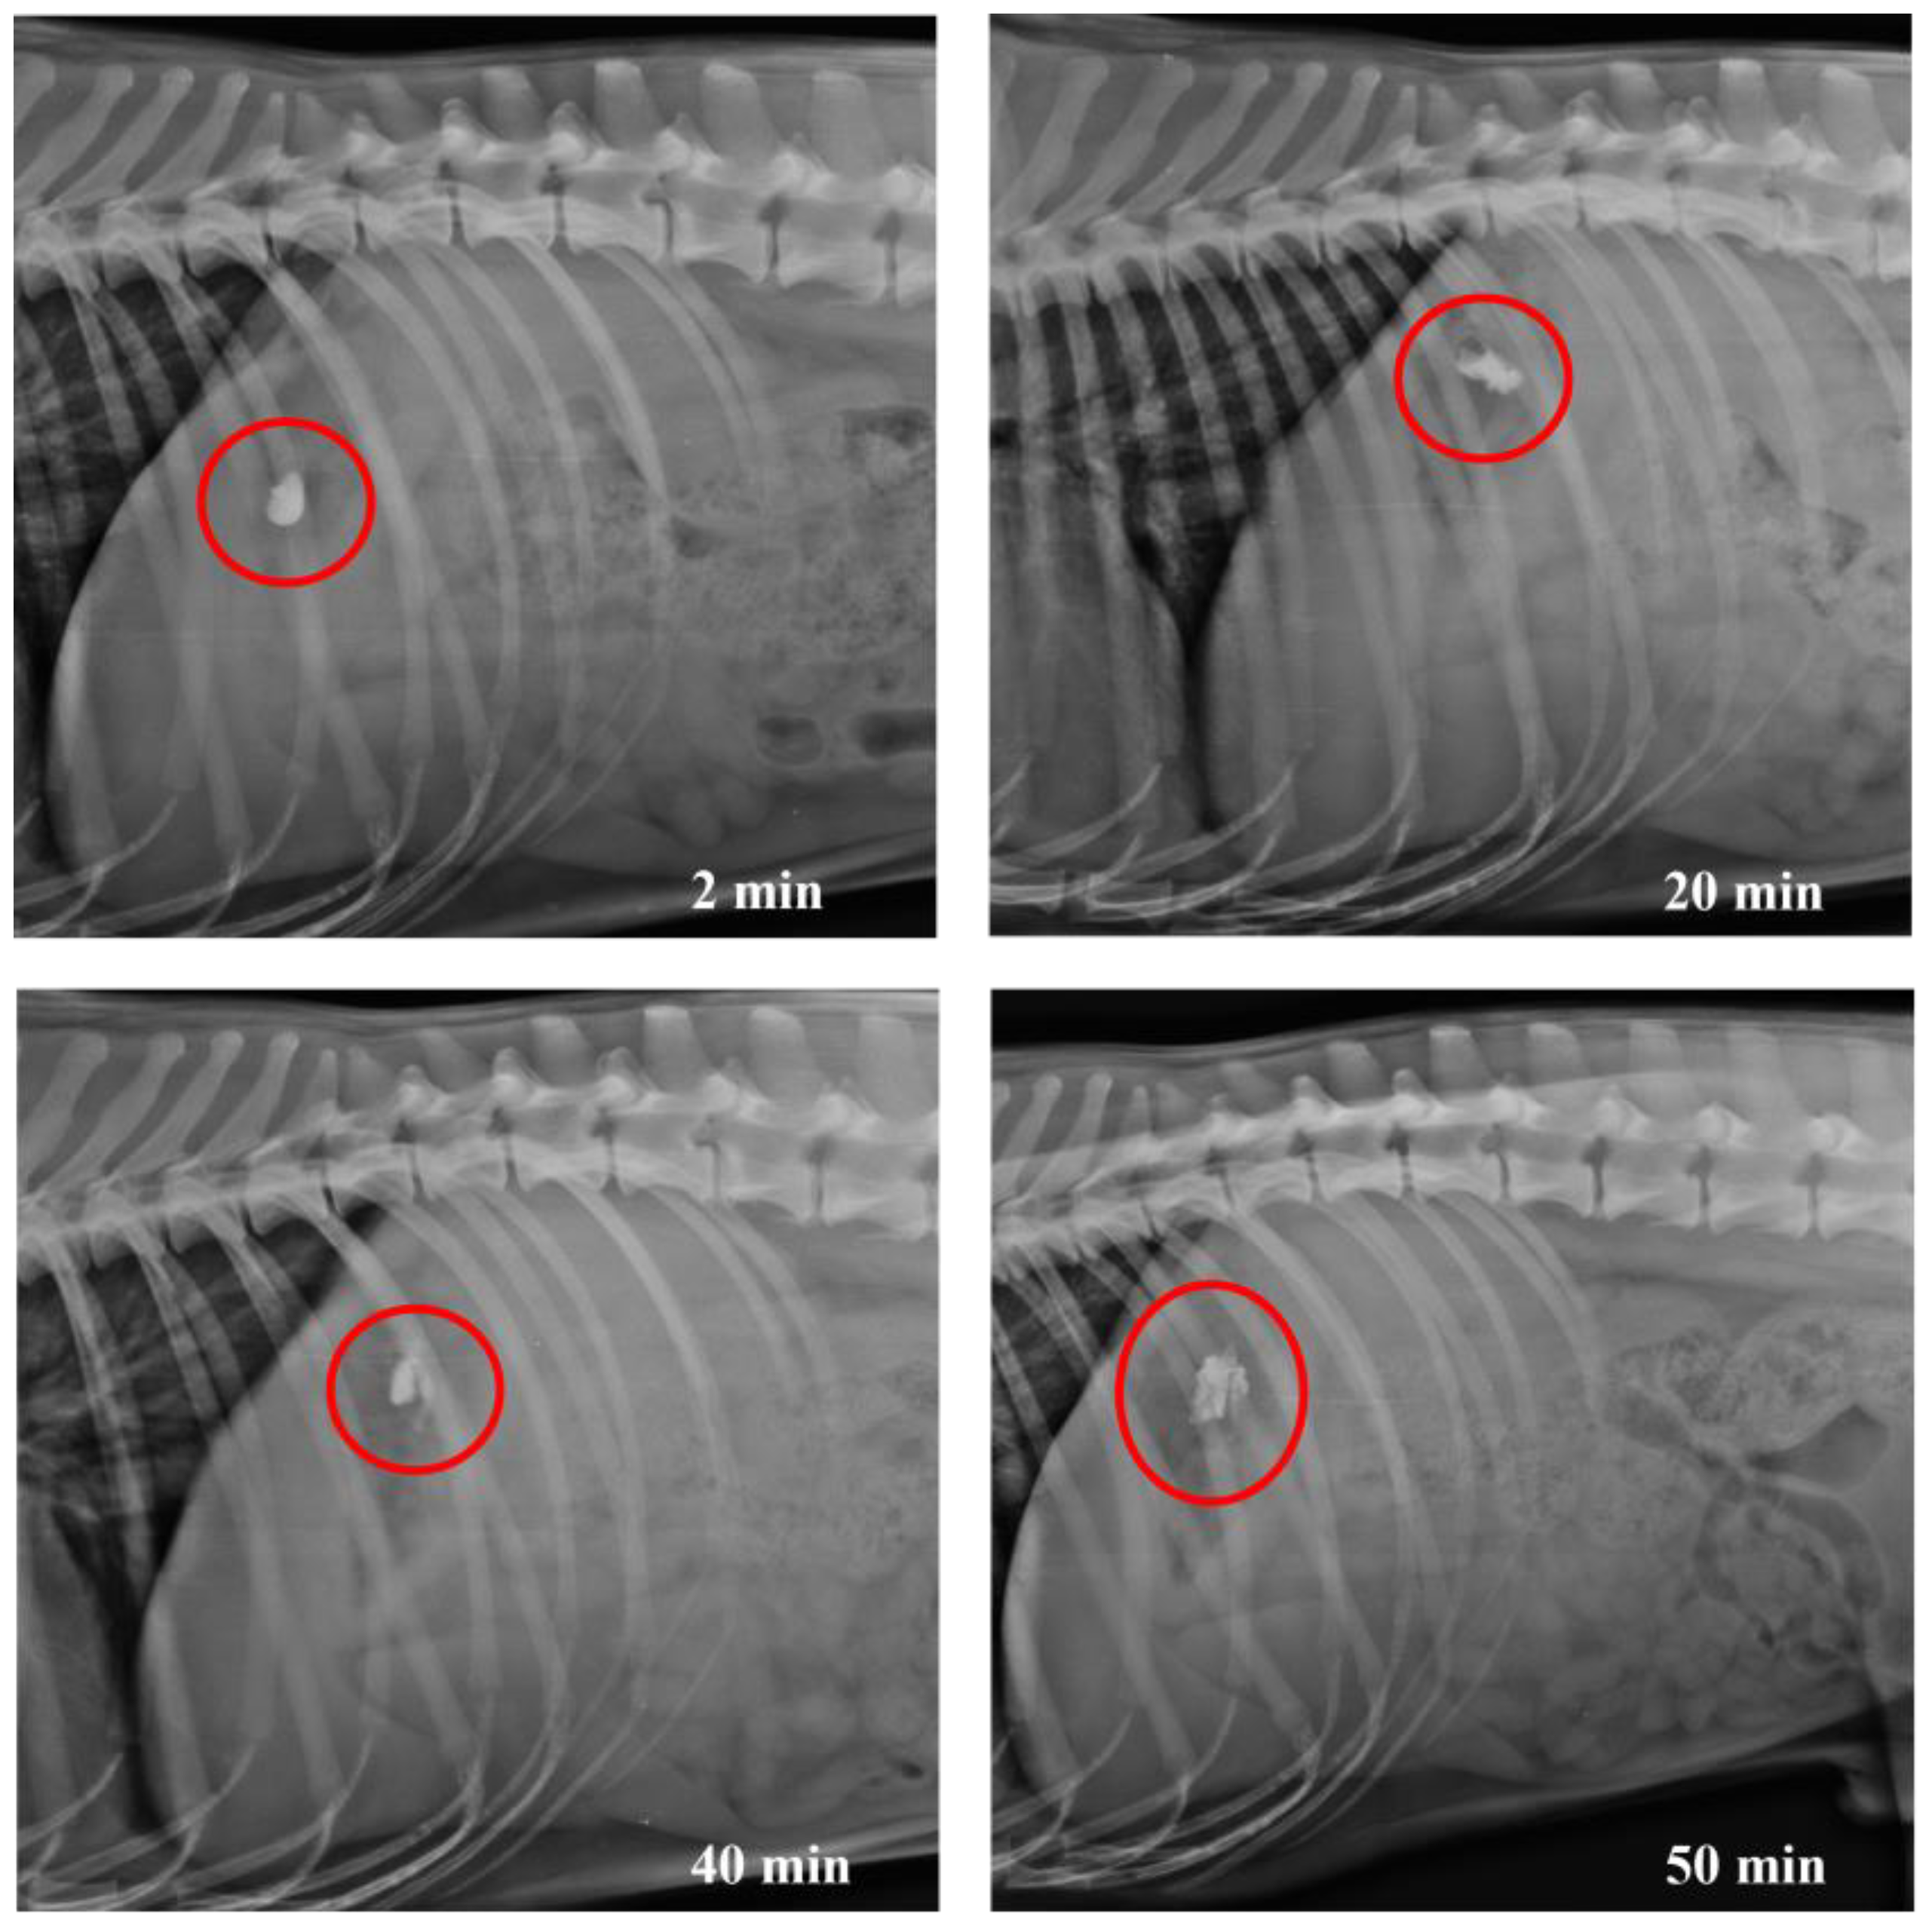

3.4. In Vivo Studies